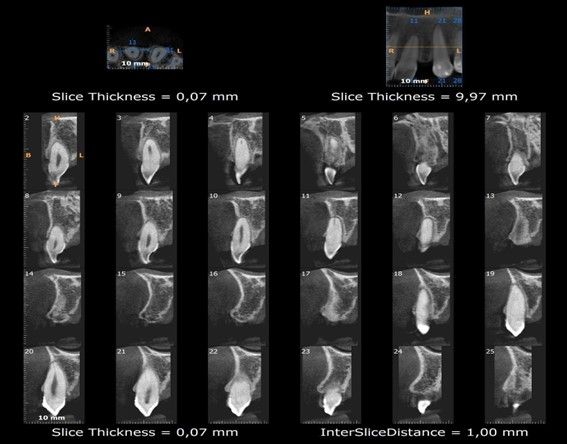

Finalizado el tratamiento con ortodoncia (Figuras 3, 4 y 5), y una vez que el paciente optó por la opción del implante; se repitió el escaneado intraoral y se obtuvo un escáner de haz cónico para la correcta planificación de la cirugía implantológica (Figura 6).